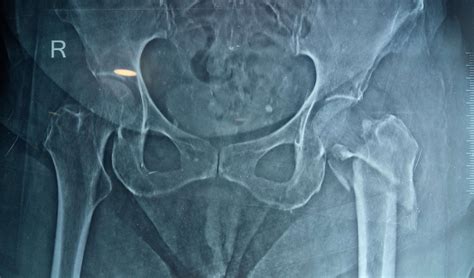

A hip fracture surgery is a critical medical procedure typically performed to repair a broken hip, which is a break in the upper quarter of the femur (thigh bone). This injury is particularly common among older adults, often resulting from falls or underlying conditions like osteoporosis that weaken the bone structure. Because a hip fracture severely limits mobility and can lead to serious complications if left untreated, prompt surgical intervention is usually the standard of care to restore function, reduce pain, and allow patients to return to their daily activities as quickly as possible.

When an individual suffers a hip fracture, the primary goal of the medical team is to stabilize the bone or replace the damaged joint to facilitate early movement. The specific type of surgery recommended depends heavily on the location and severity of the break, the patient's overall health, and their level of activity prior to the injury. Orthopedic surgeons evaluate these factors to determine the best approach, which generally falls into three main categories: internal fixation, partial hip replacement, or total hip replacement.